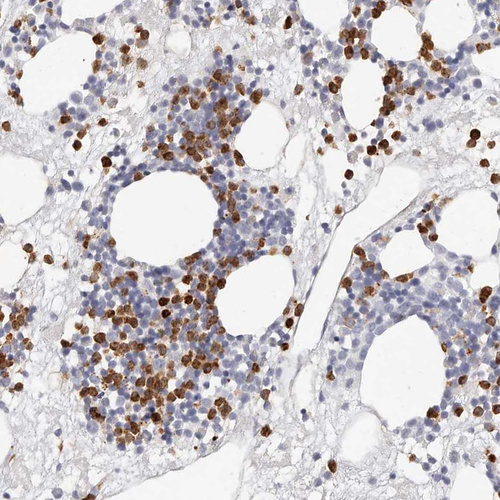

Immunohistochemistry analysis in human bone marrow and cerebral cortex tissues using HPA029874 antibody. Corresponding CAMP RNA-seq data are presented for the same tissues.